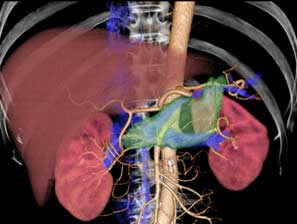

3D画像

3D画像を作成することにより、臓器と血管の関係性などをあらゆる角度から観察することができます。そのため、手術計画を立てる際などに有用な画像です。

また、臓器や血管ごとに色を変えることができ、輪切りのCT画像よりも視覚的に分かりやすいのが特徴です。